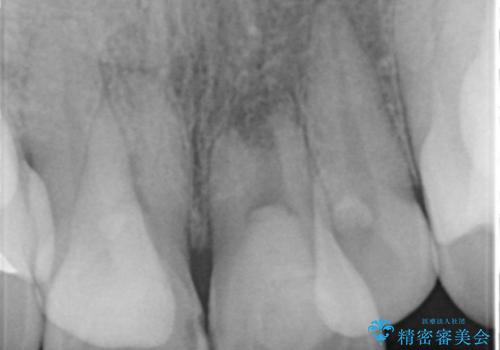

X線写真より不十分な根管治療、根尖病変、前歯の変色が認められます。

歯根の近接のみられる右上側切歯を抜去し、根管治療を伴うセラミック治療を計画します。

叢生が著しく、歯根の近接が見られる場合歯磨きができず歯石がたまりやすく骨吸収の原因となることが多いです。

このような場合矯正や転位歯の抜去が治療方法として挙げられます。